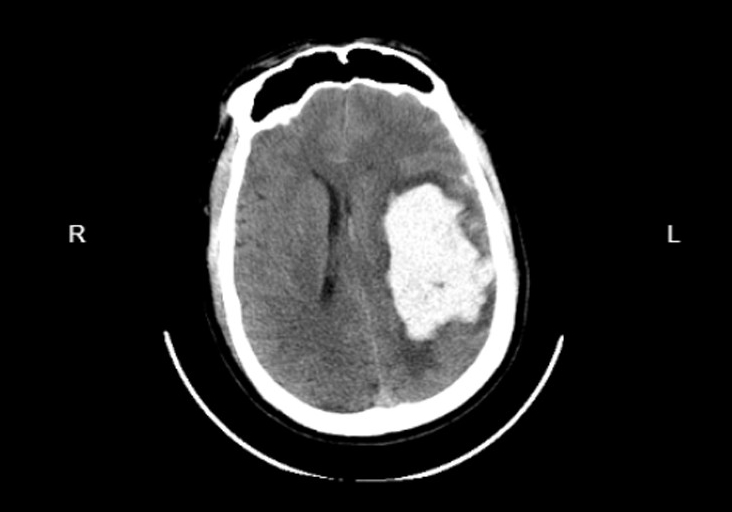

2025年5月21日上午,良先生(化名)在騎行摩托車時(shí)不慎摔落,頭部猛烈撞擊地面,當(dāng)場(chǎng)昏迷,生命垂危。在路人和120急救人員的快速反應(yīng)下,他被緊急送至紹興袍江醫(yī)院急診科。進(jìn)入搶救室時(shí),良先生意識(shí)模糊、呼之不應(yīng),昏迷程度迅速加深并出現(xiàn)呼吸抑制,情況萬(wàn)分危急。急診醫(yī)師當(dāng)機(jī)立斷,實(shí)施緊急床邊氣管插管,建立人工氣道輔助通氣,為后續(xù)救治爭(zhēng)取寶貴時(shí)間。醫(yī)護(hù)人員全程護(hù)送,緊急CT檢查顯示:大腦實(shí)質(zhì)密度減低,左側(cè)額顳頂硬膜下出血、右側(cè)硬膜外血腫、蛛網(wǎng)膜下腔出血,合并右側(cè)顱骨及顳骨多發(fā)骨折。最2025-06-09

PART01危重患者緊急入院4月18日凌晨3時(shí),一名因醉酒摔倒致頭部外傷、意識(shí)模糊的患者被緊急送至我院急診科。入院時(shí)患者頭部持續(xù)出血、右側(cè)肢體偏癱,頭顱CT檢查提示“左側(cè)額葉腦挫裂傷合并左側(cè)額顳部硬膜下血腫”,病情危重。凌晨3點(diǎn)急診CT神經(jīng)外科團(tuán)隊(duì)迅速響應(yīng),嚴(yán)密監(jiān)測(cè)患者生命體征。然而,隨著時(shí)間推移,患者頭痛加劇,復(fù)查CT顯示顱內(nèi)血腫范圍擴(kuò)大,腦組織受壓明顯,需立即手術(shù)干預(yù)。上午9點(diǎn)CT復(fù)查PART02血腫擴(kuò)大危及生命面對(duì)緊急情況,神經(jīng)外科趙堅(jiān)柱副主任醫(yī)師帶領(lǐng)團(tuán)隊(duì)快速制定手術(shù)方2025-04-26